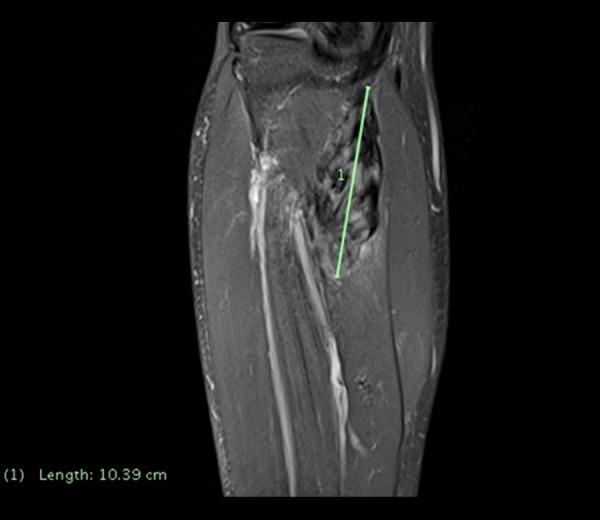

BACKGROUND Venous thromboembolism (VTE), comprising deep vein thrombosis (DVT) and pulmonary embolism (PE), is a common, serious cardiovascular event. Predisposing factors include genetic disorders, immobility, and underlying malignancy. Soft tissue tumors are by contrast rare, but should be included in the differential etiology of DVT, especially when the patient is young and has few thrombotic risk factors. CASE REPORT We present a 40-year-old patient whose initial diagnosis was spontaneous DVT of the lower leg, treated conventionally. Subsequently, he developed progressive calf swelling, which was diagnosed as multifocal desmoid fibromatosis, a rare and complex soft tissue tumor. CONCLUSIONS DVT is common but soft tissue tumors are rare. The disparity in incidence of these very distinct pathologies may contribute to late diagnosis of occult soft tissue pathology. We discuss the incidence, etiology, pathology, diagnosis, and best management of both desmoid fibromatosis and DVT, which may co-exist in a causative way.

背景 静脉血栓栓塞症(VTE),包括深静脉血栓形成(DVT)和肺栓塞(PE),是一种常见且严重的心血管事件。诱发因素包括遗传疾病、活动受限和潜在恶性肿瘤。相比之下,软组织肿瘤较为罕见,但在DVT的鉴别病因中应予以考虑,尤其是当患者年轻且血栓形成风险因素较少时。病例报告 我们介绍了一名40岁患者,其最初诊断为小腿自发性DVT,接受了常规治疗。随后,他出现了进行性小腿肿胀,被诊断为多灶性硬纤维瘤病,这是一种罕见且复杂的软组织肿瘤。结论 DVT很常见,但软组织肿瘤罕见。这些截然不同的病理情况在发病率上的差异可能导致隐匿性软组织病变的延迟诊断。我们讨论了硬纤维瘤病和DVT的发病率、病因、病理、诊断及最佳治疗方法,它们可能以因果关系并存。